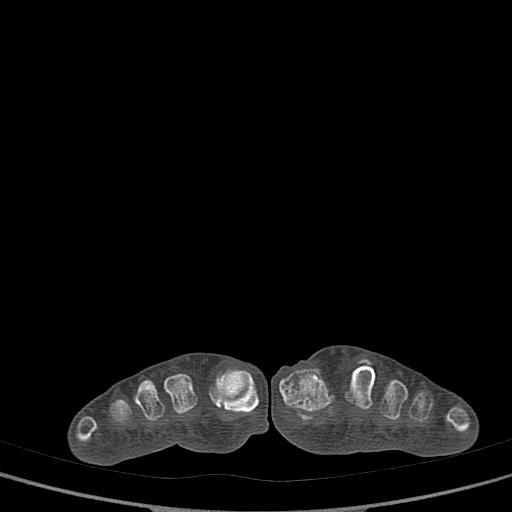

标题: CT13415:M72Y,跖趾关节病变,请会诊 [打印本页]

标题: CT13415:M72Y,跖趾关节病变,请会诊

男72岁左侧跖趾关节肿痛15年,查压痛。

骨软骨瘤可能性大,请上传x光片.

考虑退行性骨关节病。